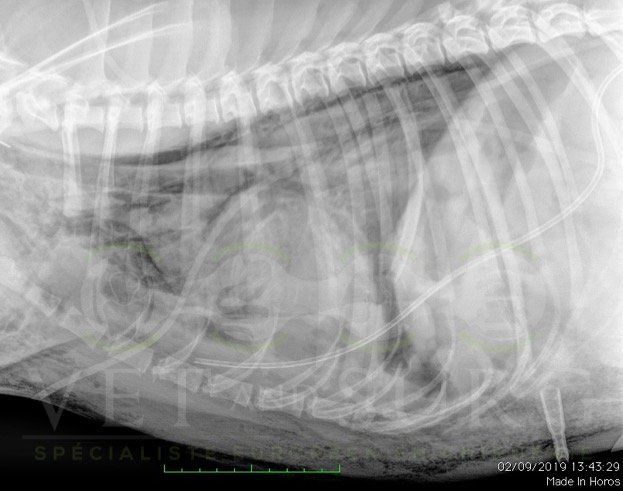

Dans la gestion des pathologies respiratoires, cardio-vasculaires, et des atteintes médiastinales et diaphragmatiques.